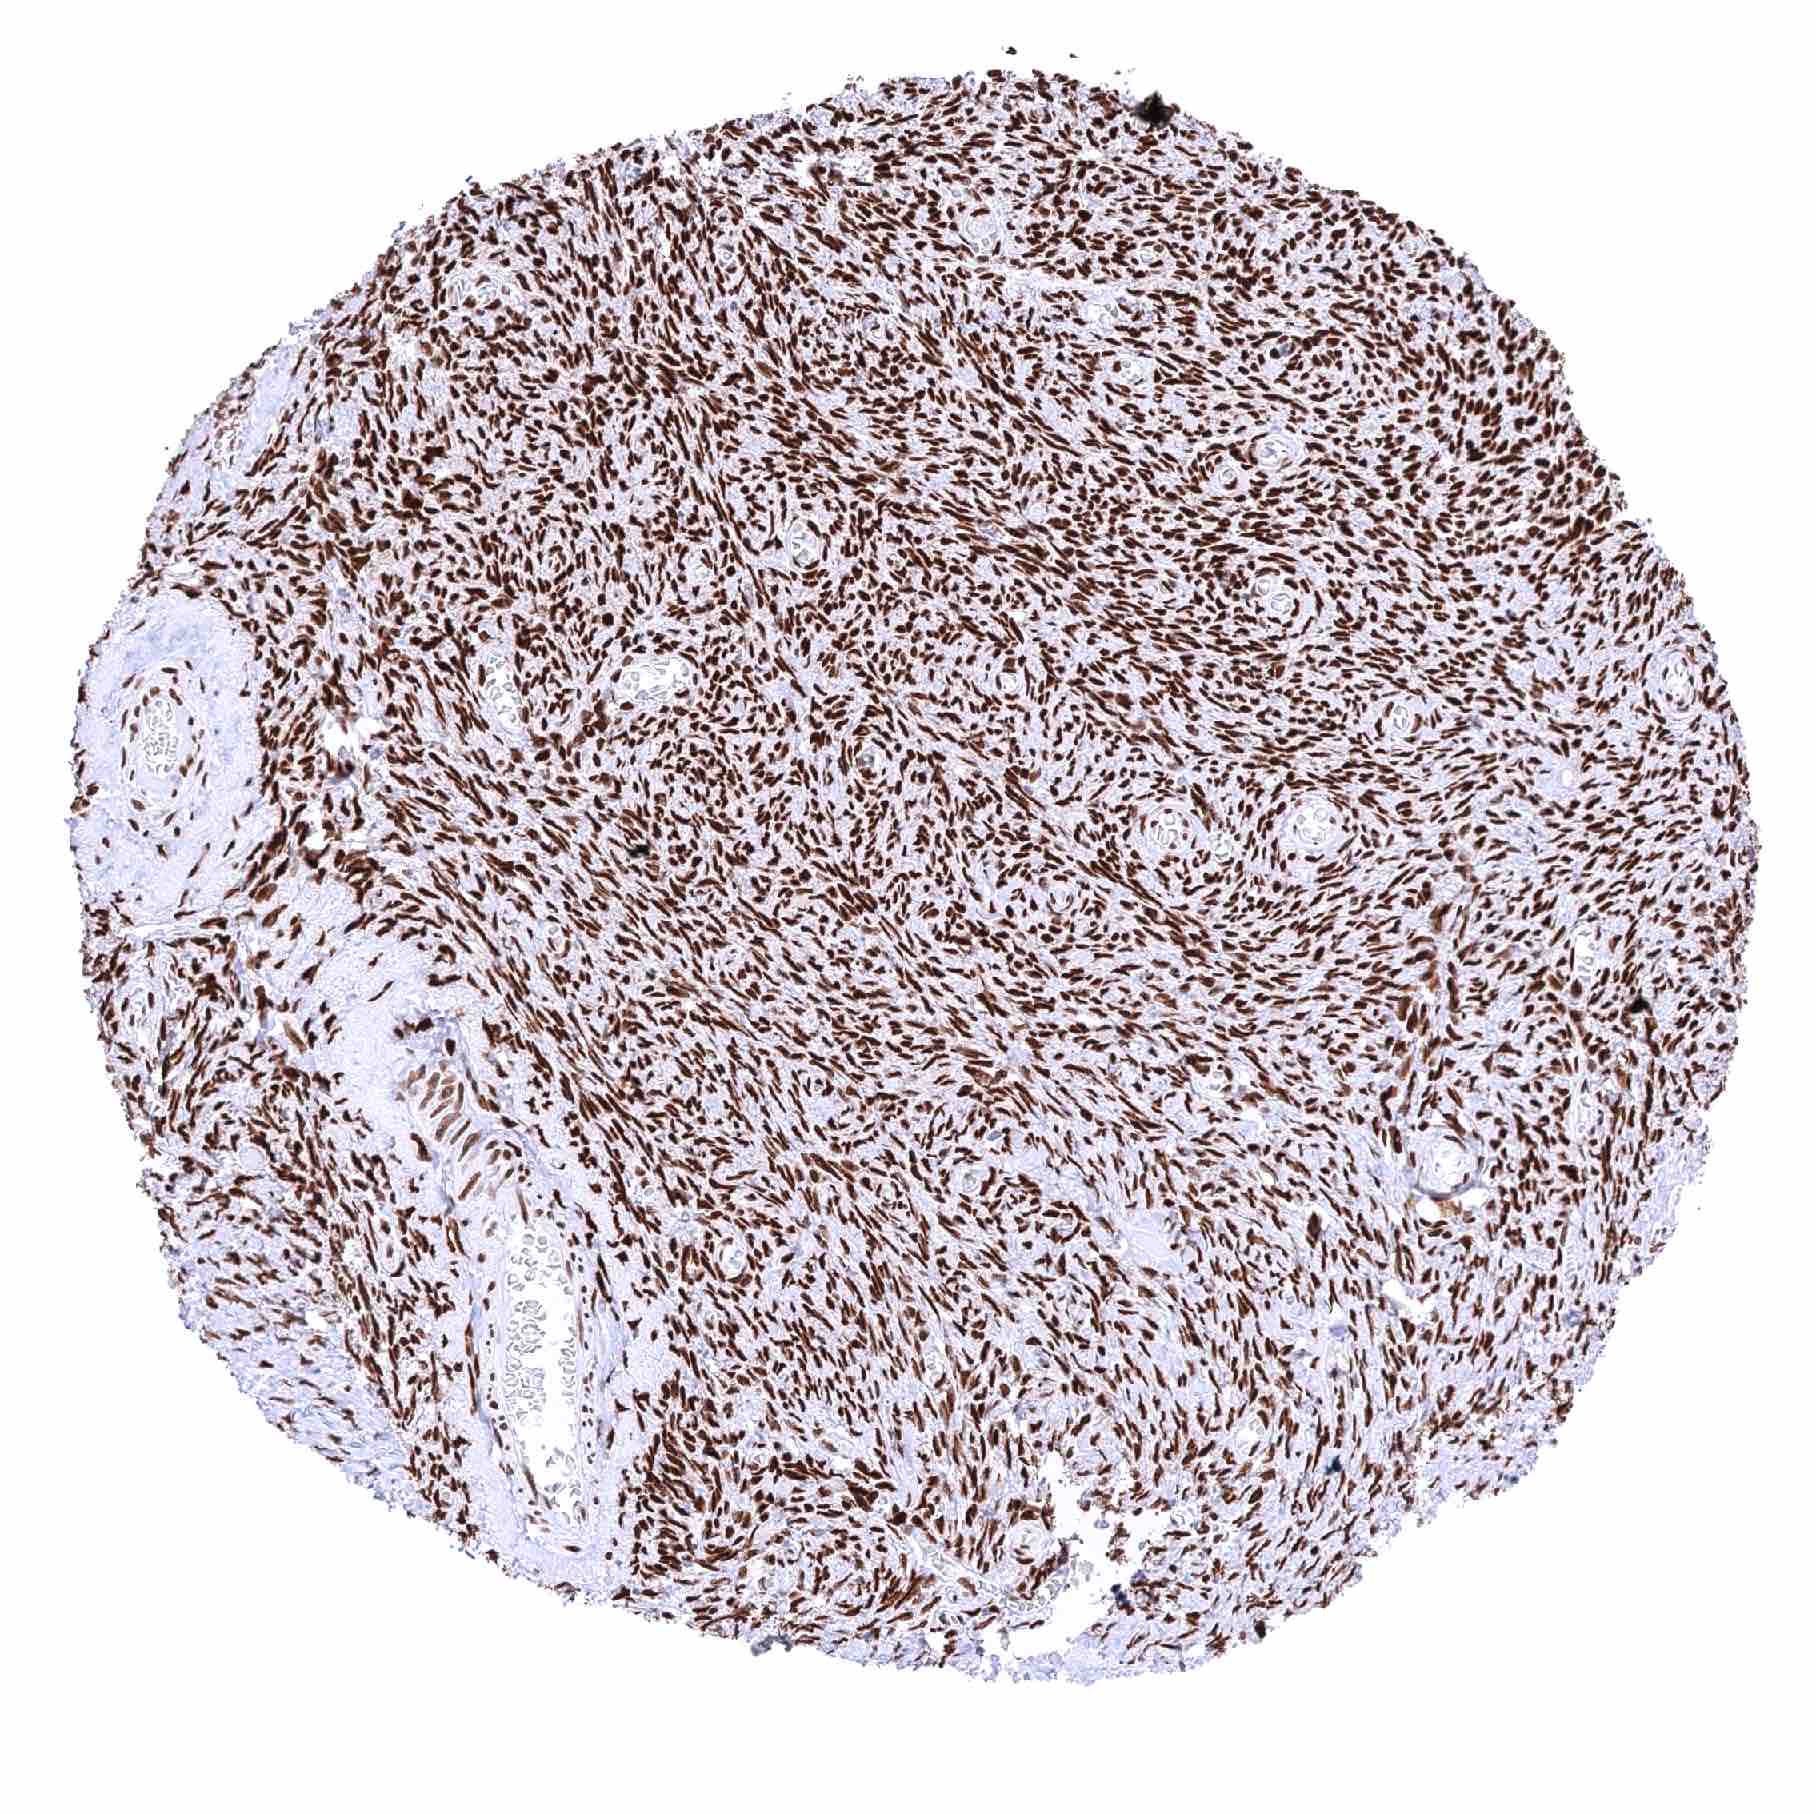

| Urinary bladder, muscular wall – Distinct nuclear staining of smooth muscle cells and of other cell types |